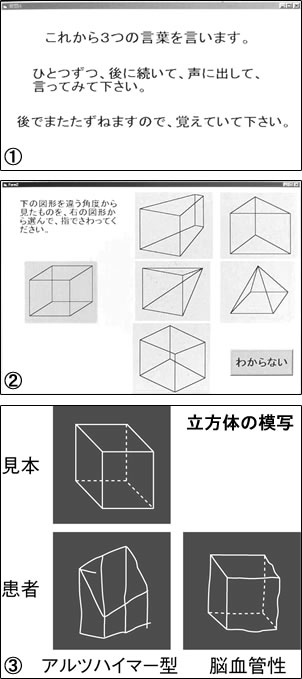

しかし認知症には早期発見するよい器械がありませんでした。そこで私たちはコンピューターを使ったタッチパネル式の器械を開発しました。画面を指でポン ポンとさわり、聞かれた質問に答えるだけの簡単なものです。最初は「桜」「梅」「電車」など3つの言葉を声に出して覚えてもらいます(①)。

次に月日、曜日、年を聞きます。日にちは毎日変わるので、自分の状況を把握する力(見当識)がしっかりしてないと答えられません。

空間認知能力も試します。見本の絵と同じ絵を、5つの中から選びます(②)。立方体も模写してもらいます。アルツハイマー型の方は脳血管性と比べ、比較的早期から空間認知機能が悪くなり、うまく図がかけなくなります(③)。

最後に、最初に覚えてもらった言葉を3つ選んでもらいます。認知症の方は「さあ、何だったかな」ということになってしまいます。